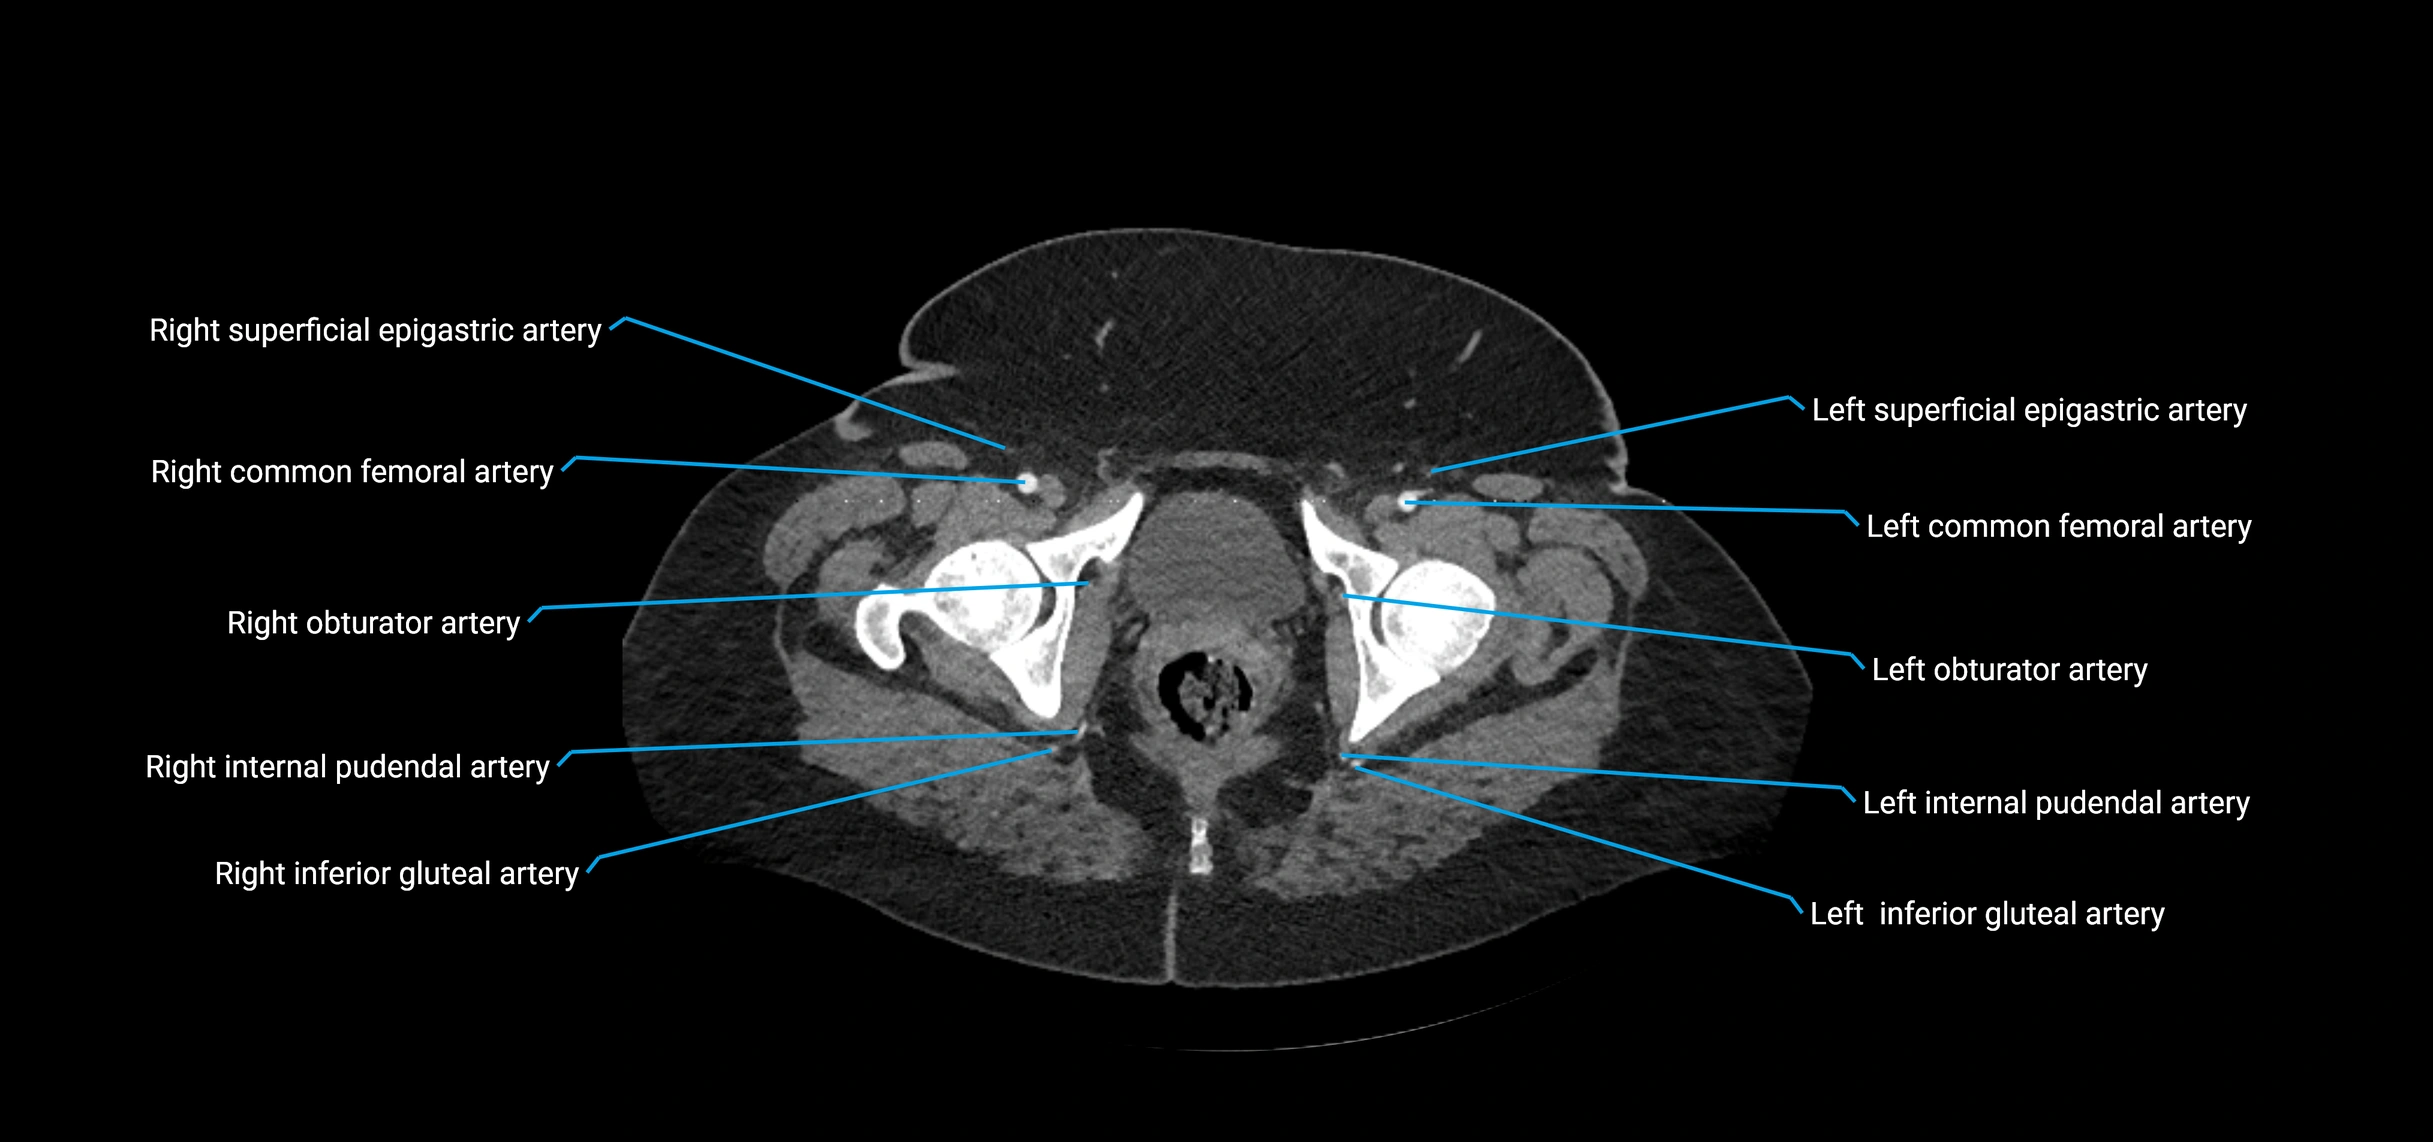

Contrast-enhanced CT (CTA):

• Gold standard for abdominal aortic imaging

• Provides excellent detail of lumen, wall, aneurysm, thrombus, and branch vessels

• Multiplanar and 3D reconstructions help in aneurysm measurement, stent graft planning, and dissection evaluation